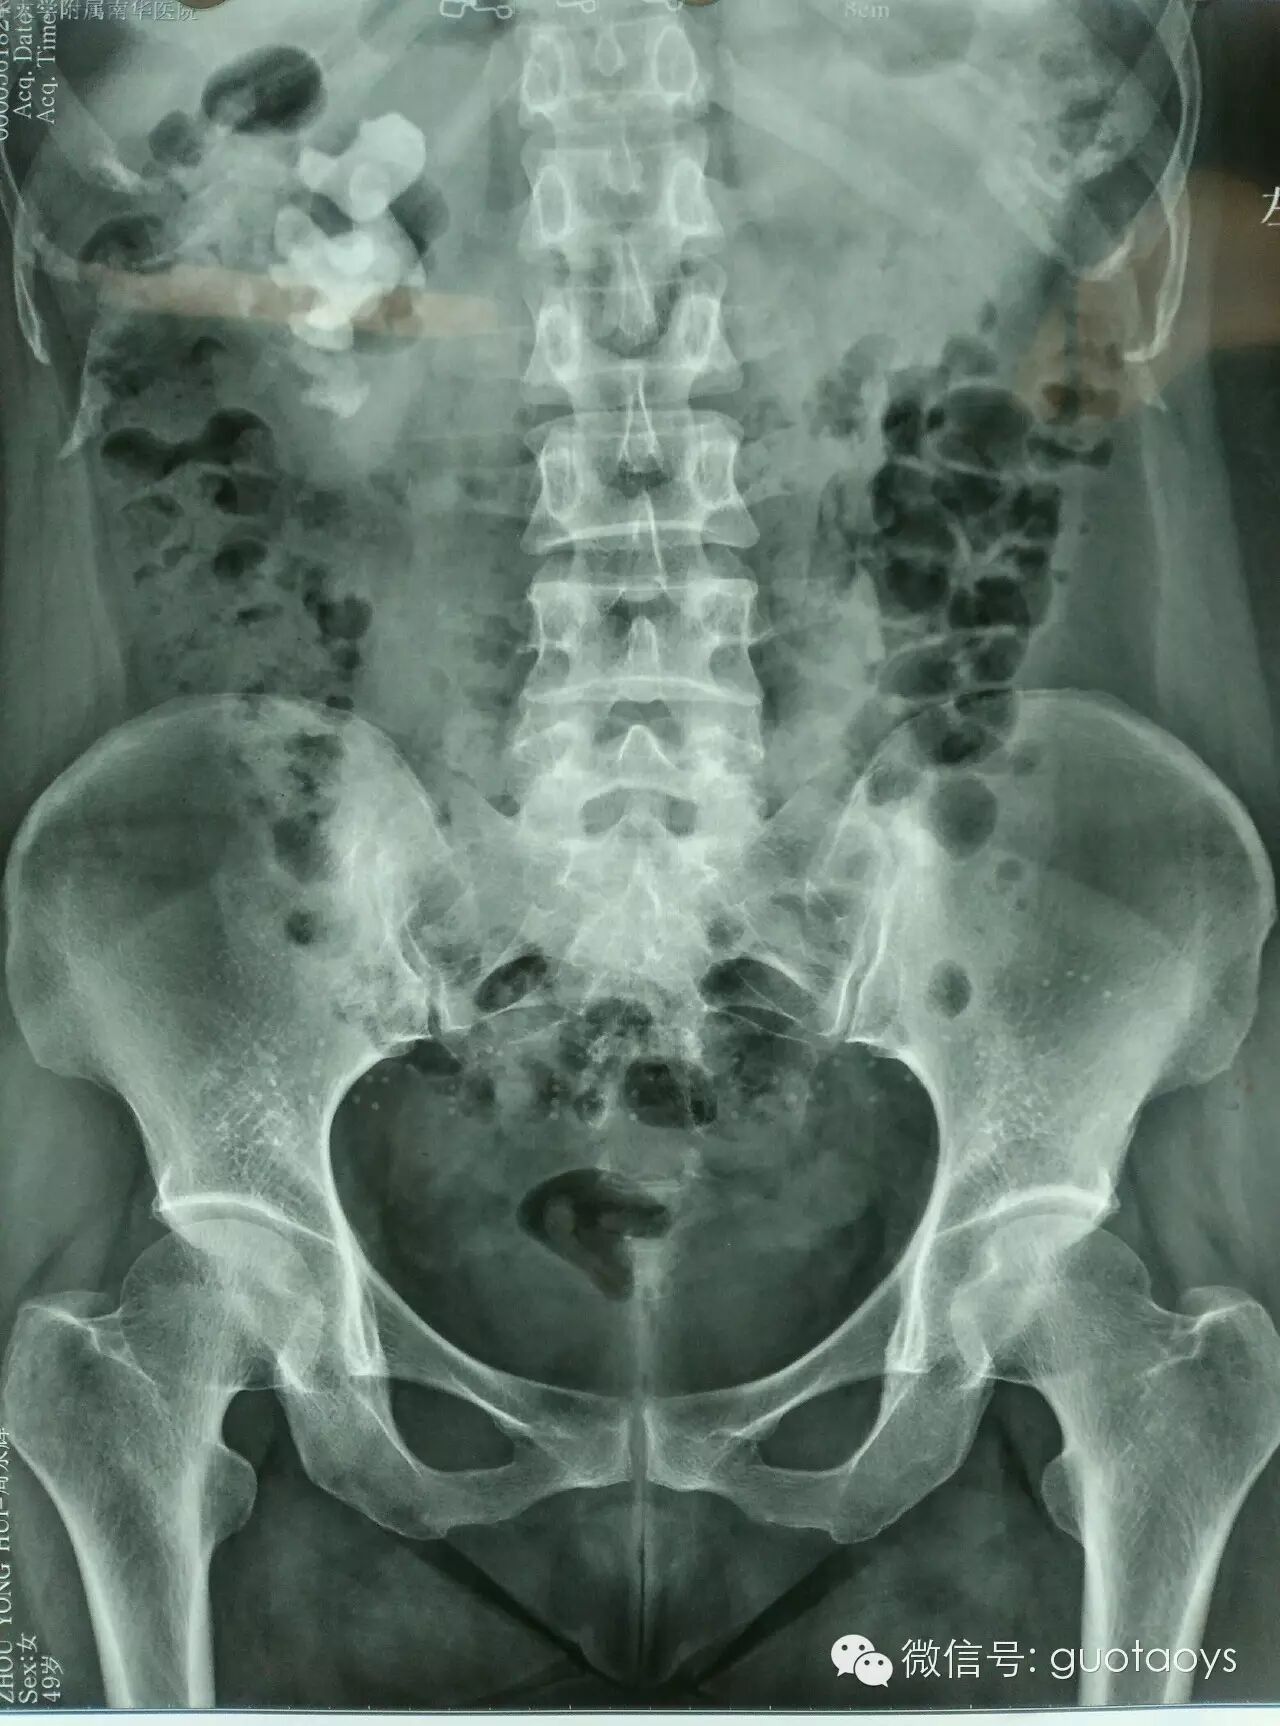

术前CT